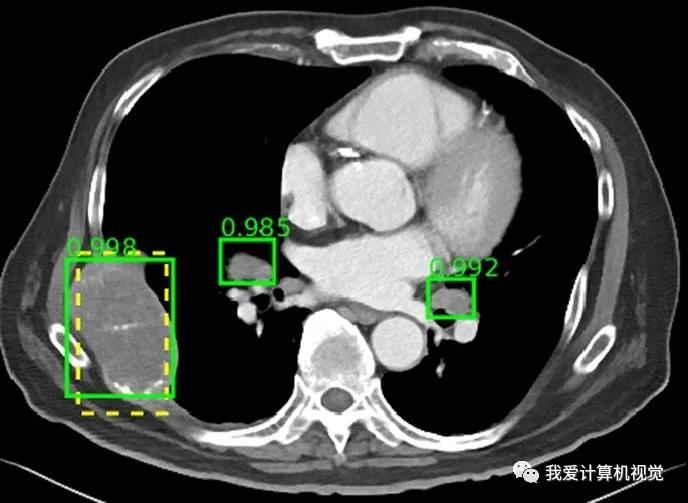

该数据库中图像包括多种病变类型,包括肾脏病变,骨病变,肺结节和淋巴结肿大。缺乏多类别病变数据集,一直是开发能够检测多种病变类型的更通用CADe框架的主要障碍。而DeepLesion多类别病变数据集可以用来开发自动化放射诊断的CADx系统。

除了构建数据库,该团队还开发了基于数据库的通用病变检测器。研究人员指出,病变检测对于放射科医师来说是一项耗时的任务,但却是诊断的关键部分。该检测器可以作为放射科医师或其他专业CADe系统的初始筛查工具。除了病变检测之外,DeepLesion数据库还可用于对病变进行分类,或基于字符串查询检索病变,或基于数据库中的现有模式预测新病例中的病变增长。未来的工作将包括将数据库扩展到其他图像模式,如MR,合并来自多家医院的数据,以及提高检测器算法的检测精度。